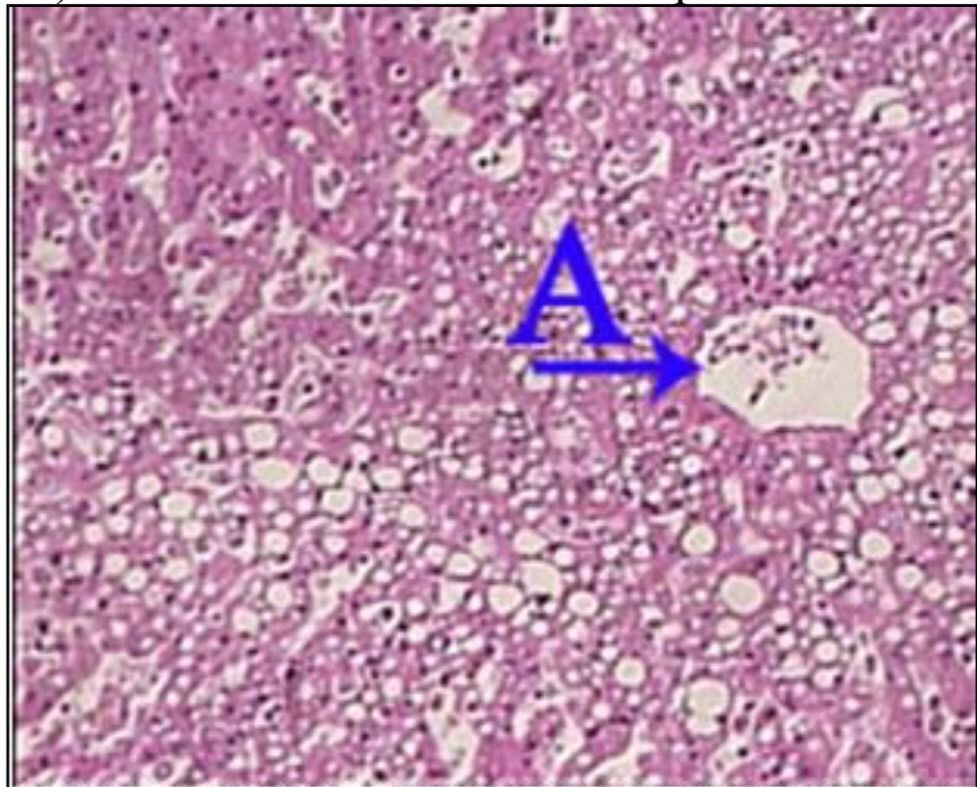

Question 11

Question

What is the correct answer at point A?

Answer

• - travées de sclérose annulaire

• - nodule cirrhotique, sans veine Centro lobulaire

• - néoformation canalicule biliaire

• - infiltration lymphocytaire

• - hépatocyte contenant de la bile

Question 12

What is the correct answer at point B?

Question 13

What is the correct answer at point C?

Question 14

What is the correct answer at point D?

Question 15

What is the correct answer at point E?